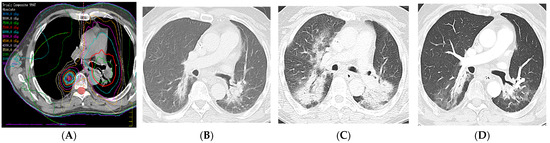

7.2. Radiation Recall Pneumonitis

- McGovern, K.; Ghaly, M.; Esposito, M.; Barnaby, K.; Seetharamu, N. Radiation recall pneumonitis in the setting of immunotherapy and radiation: A focused review. Future Sci. OA 2019, 5, FSO378. [Google Scholar] [CrossRef] [PubMed]

- Teng, F.; Li, M.; Yu, J. Radiation recall pneumonitis induced by PD-1/PD-L1 blockades: Mechanisms and therapeutic implications. BMC Med. 2020, 18, 275. [Google Scholar] [CrossRef]